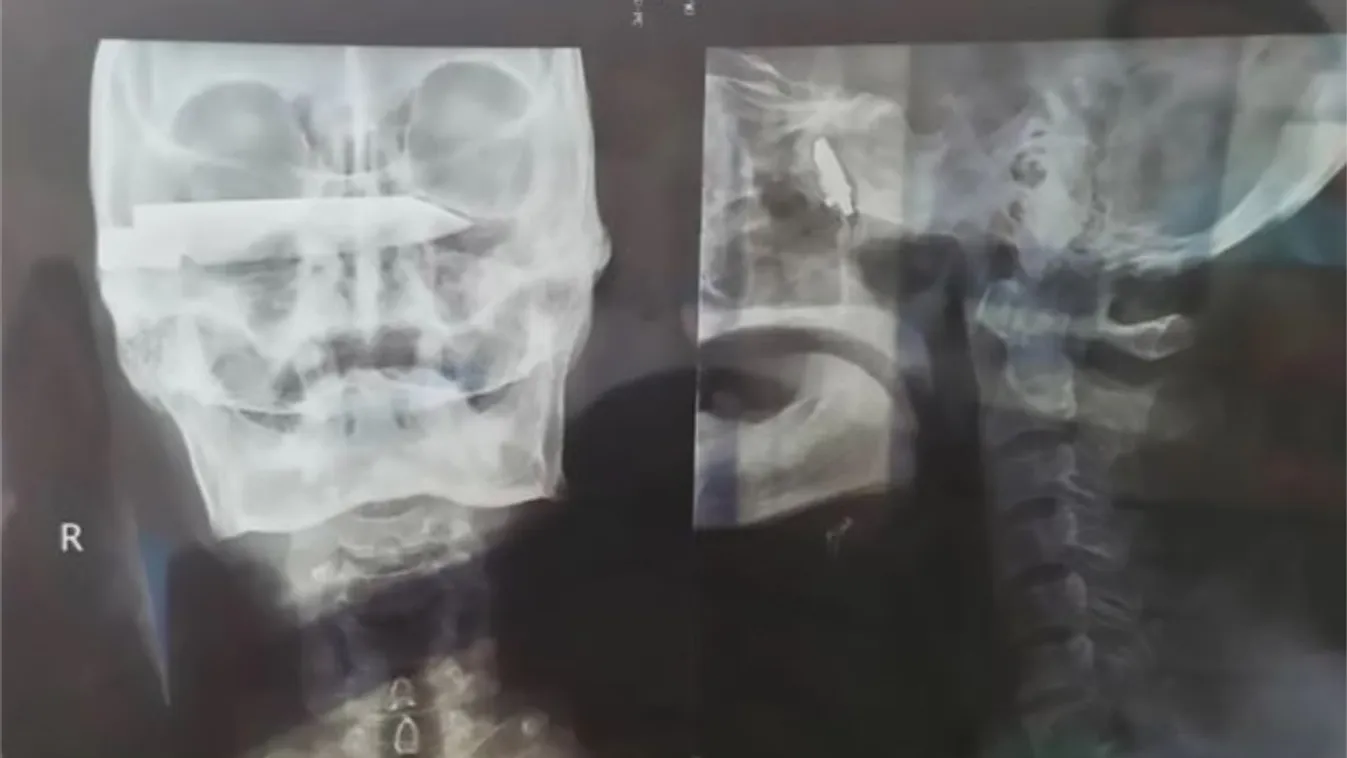

Az 1990-es években megtámadtak egy kínai kecskepásztort, és azóta egy 10 centis késsel a koponyájában mászkált. A 76 éves férfit most műtötték meg, de még az orvosok is elámultak, amikor meglátták a röntgenképét.

A férfinak a csodával határos módon csak 2012-ben okozott panaszt a kés, akkor borzalmas fejfájással fordult orvoshoz. De akkor nem merték megműteni, mert nem találtak megfelelő specialistát.

Idén április 2-án és 8-án megműtötték és sikeres volt a beavatkozás – írta a Daily Star.